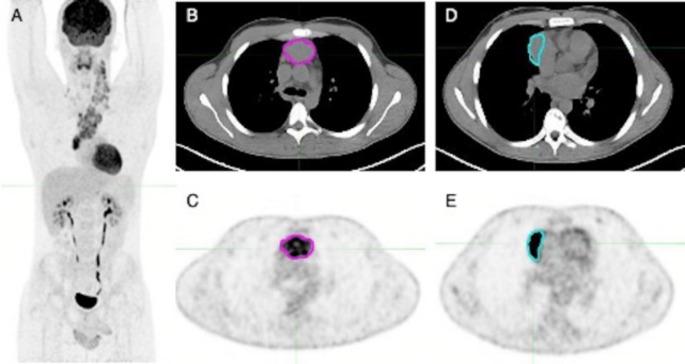

In a previous preliminary study, radiomic features from the largest and the hottest lesion in baseline F-FDG PET/CT (bPET/CT) of classical Hodgkin's Lymphoma (cHL) predicted early response-to-treatment and prognosis. Aim of this large retrospectively-validated study is to evaluate the predictive role of two-lesions radiomics in comparison with other clinical and conventional PET/CT models. cHL patients with bPET/CT between 2010 and 2020 were retrospectively included and randomized into training-validation sets. Target lesions were: Lesion_A, with largest axial diameter (D); Lesion_B, with highest SUV. Total-metabolic-tumor-volume (TMTV) was calculated and 212 radiomic features were extracted. PET/CT features were harmonized using ComBat across two scanners. Outcomes were progression-free-survival (PFS) and Deauville Score at interim PET/CT (DS). For each outcome, three predictive models and their combinations were trained and validated: - radiomic model "R"; - conventional PET/CT model "P"; - clinical model "C". 197 patients were included (training = 118; validation = 79): 38/197 (19%) patients had adverse events and 42/193 (22%) had DS ≥ 4. In the training phase, only one radiomic feature was selected for PFS prediction in model "R" (Lesion_B F_cm.corr, C-index 66.9%). Best "C" model combined stage and IPS (C-index 74.8%), while optimal "P" model combined TMTV and D (C-index 63.3%). After internal validation, "C", "C + R", "R + P" and "C + R + P" significantly predicted PFS. The best validated model was "C + R" (C-index 66.3%). No model was validated for DS prediction. In this large retrospectively-validated study, a combination of baseline F-FDG PET/CT two-lesions radiomics and other conventional models showed an added prognostic power in patients with cHL. As single models, conventional clinical parameters maintain their prognostic power, while radiomics or conventional PET/CT alone seem to be sub-optimal to predict survival.

在之前的一项初步研究中,经典型霍奇金淋巴瘤(cHL)基线F-FDG PET/CT(bPET/CT)中最大且最热点状病变的放射组学特征可预测早期治疗反应和预后。这项大型回顾性验证研究的目的是评估双病变放射组学与其他临床及传统PET/CT模型相比的预测作用。回顾性纳入了2010年至2020年间进行bPET/CT检查的cHL患者,并随机分为训练-验证集。目标病变为:病变A,具有最大轴向直径(D);病变B,具有最高SUV。计算总代谢肿瘤体积(TMTV)并提取212个放射组学特征。使用ComBat对两台扫描仪的PET/CT特征进行标准化。观察指标为无进展生存期(PFS)和中期PET/CT时的迪沃利评分(DS)。对于每个观察指标,训练并验证了三种预测模型及其组合:- 放射组学模型“R”;- 传统PET/CT模型“P”;- 临床模型“C”。纳入了197例患者(训练组 = 118例;验证组 = 79例):197例患者中有38例(19%)发生不良事件,193例患者中有42例(22%)DS≥4。在训练阶段,模型“R”中仅选择了一个放射组学特征用于PFS预测(病变B F_cm.corr,C指数66.9%)。最佳“C”模型结合了分期和国际预后评分(IPS)(C指数74.8%),而最佳“P ”模型结合了TMTV和D(C指数63.3%)。经过内部验证,“C”、“C + R”、“R + P”和“C + R + P”显著预测了PFS。验证效果最佳的模型是“C + R”(C指数66.3%)。没有模型被验证可用于DS预测。在这项大型回顾性验证研究中,基线F-FDG PET/CT双病变放射组学与其他传统模型的组合在cHL患者中显示出额外的预后预测能力。作为单一模型,传统临床参数保持其预后预测能力,而单独的放射组学或传统PET/CT在预测生存方面似乎并不理想。